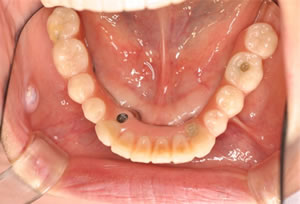

奥歯に骨がないので、オールオン4で即時荷重(インプラント手術をした日に仮歯がはいる)をおこないました。

治療後